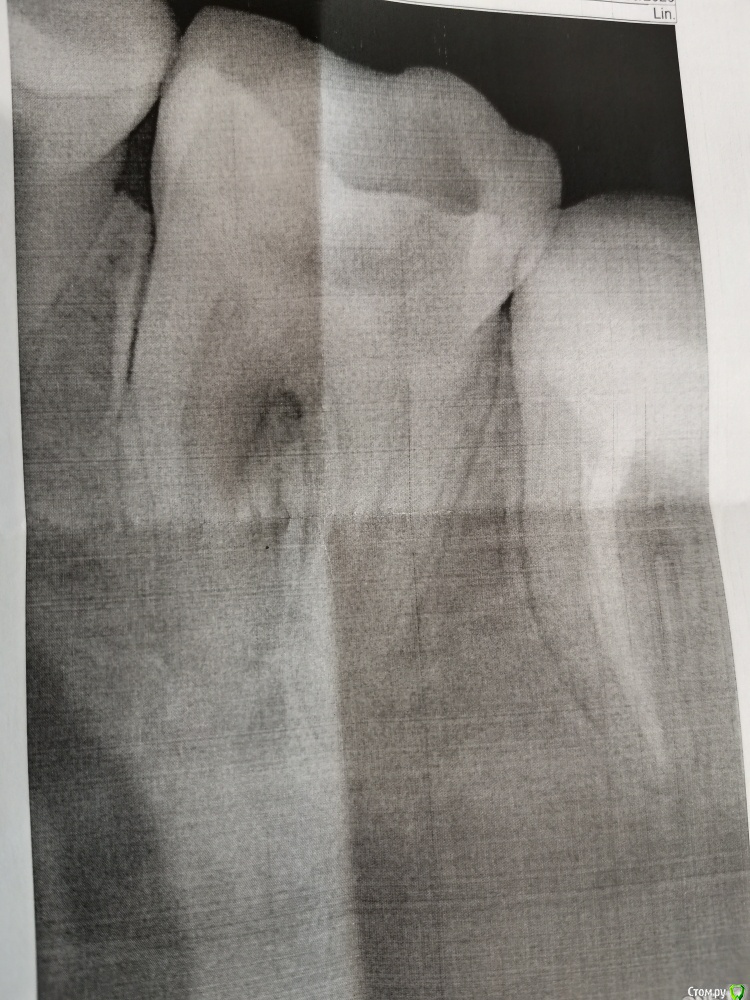

Ffgtrigun Опубликовано 22 июня, 2020 Поделиться Опубликовано 22 июня, 2020 Добрый деньПрошу совета:1) 03.06 назначили упражнения для шейного отдела. Одно из: ладонь на внешний угол челюсти, и наклонять голову, а ладонью устроить противовес. Через три дня, заболела нижняя челюсть с левой стороны, подумала, что порезала пломбой десну. Два дня понаблюдала, затем четыре дня прикладывала один раз в день тампон с мараславином на пять минут. Боль была тупая и тянущая, иногда пульсирующая, но терпимая, спать не мешала, при надавливание боль пропадала совсем, обезболивающие не принимала. 16.06 боль стала резкой, длительной , при смене положения тела боль усиливалась. Выпила 250 мг анальгина, купировалось хорошо.2) 17.06 Посетила дежурного стоматолога, после моей истории, решили, что само пройдет, но на всякий отравила на рентген (картинка 1). Вскрывают пульпу, ставят диагноз периодонтит, один канал сказали пустой, второй поковыряли иглой, но приговаривали, что тяжело пролезть и бояться обломать инструмент и бором с насадкой лезть не стали. Отправили с открытым зубом домой до пятницы ( ближайший талон 26.06), наказали полоскать чуть горячим содовым раствором 6-8 раз в день. После полоскания боль становилась невыносимой и длительно не утихала (при этом болело все на левой стороне снизу), пила анальгин. При смене положения тела боль также усиливалась.3) 22.06 обратилась к стоматологу, сделали еще один снимок(картинка 2). сказали, что корни и периодонтит залечить можно, каналы нужно пломбировать и у меня бифруктация, киста может расти, но залезть туда не смогут и полечить. Шансы, после очистки каналов, на сохранение зуба 50\50. Дальше понятно только удалять. Мне 28 лет и совершенно не хочется удалять. Подскажите, как увеличить шансы на спасения зуба? Стоит ли вкладывать в зуб или лучше уже деньги на вставной отложить? Я в г. Ульяновске может есть тут волшебник, что спасет зуб.И если можно на пальцах, как так могло получиться: посещаю стоматолога раз в полгода(она кстати не рада говорит, что можно и раз в год, поэтому стала ходить к разным) полоскаю полость рта после каждого приема пищи(нормальных приемов, после перекуса нет), пользуюсь раз в день зубной лентой(нить не подошла, близко зубы), приобрела ирригатор (десна правда с трудом привыкают), раз в год панорамный снимок или КТ. Мне обидно и страшно. Ссылка на комментарий

St. Опубликовано 22 июня, 2020 Поделиться Опубликовано 22 июня, 2020 Добрый день. Снимки не совсем хорошего качества.. но показаний к удалению зуба не увидела. Нужно качественно полечить каналы, в таком случае прогноз хороший.А удалить зуб всегда успеете, это крайняя мера когда других вариантов нет Ссылка на комментарий